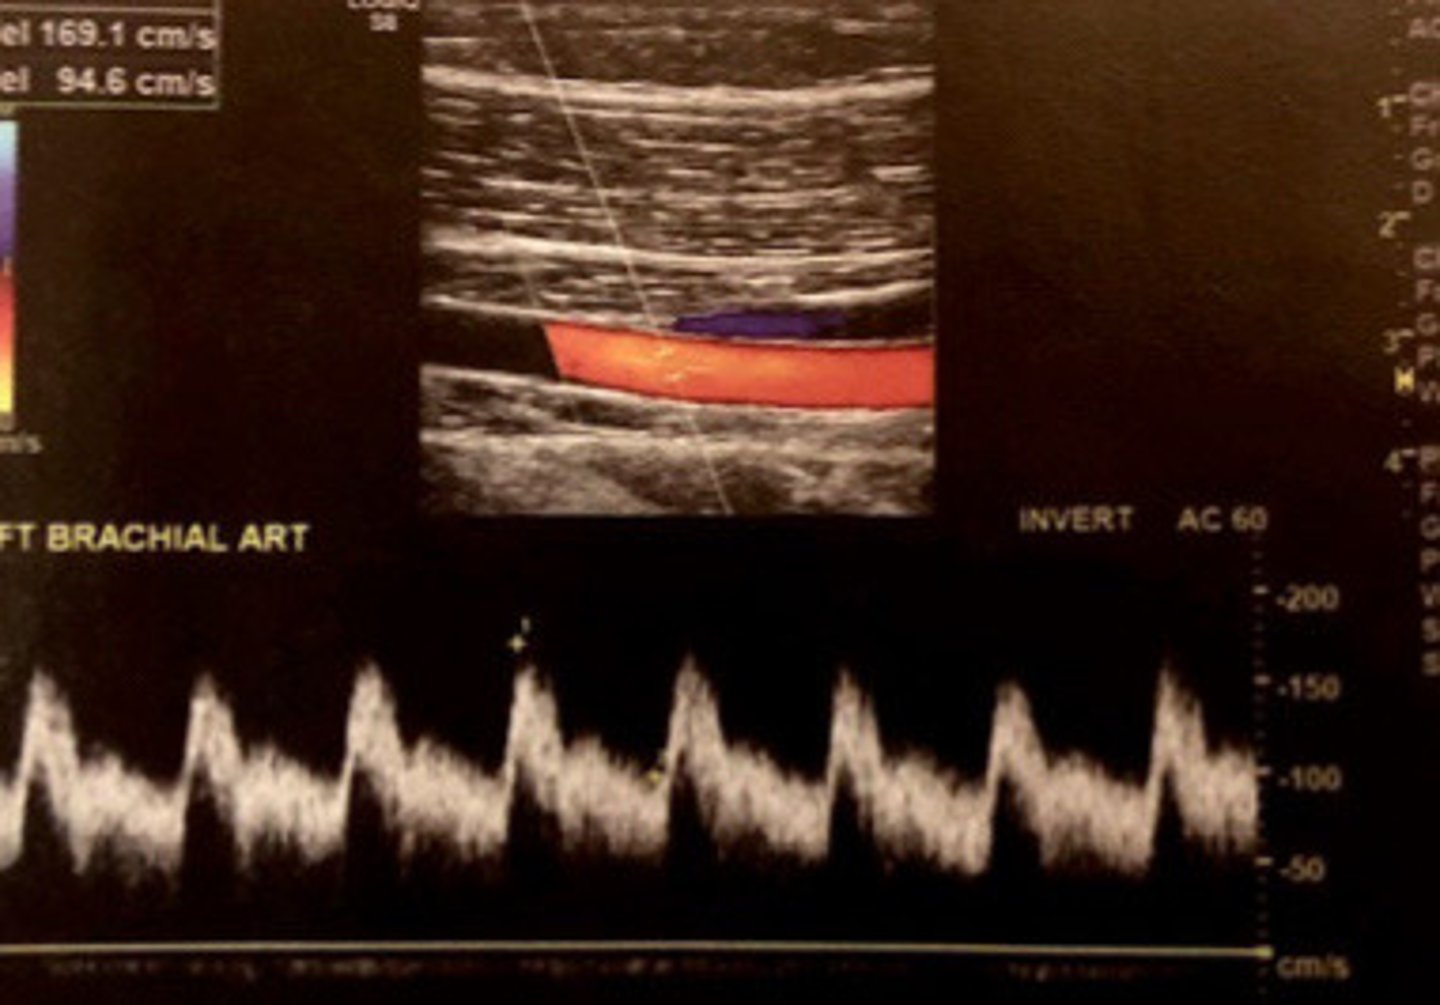

Low resistance before and within the graft with constant antegrade flow

Describe the waveform of the fistula and graft

Normal flow in fistula or graft

What does this image show

<400cm/s

What is the normal PSV for grafts and fistulas

Normal PSV in a graft/fistula